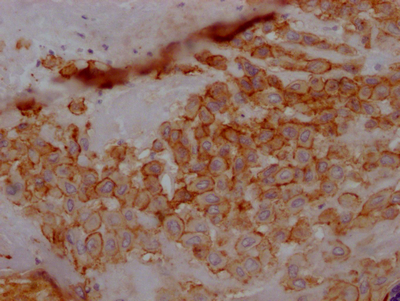

IHC image of CSB-RA902876A0HU diluted at 1:100 and staining in paraffin-embedded human placenta tissue performed on a Leica BondTM system. After dewaxing and hydration, antigen retrieval was mediated by high pressure in a citrate buffer (pH 6.0). Section was blocked with 10% normal goat serum 30min at RT. Then primary antibody (1% BSA) was incubated at 4℃ overnight. The primary is detected by a Goat anti-rabbit IgG polymer labeled by HRP and visualized using 0.05% DAB.